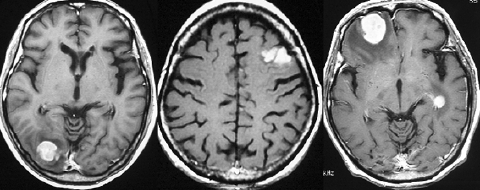

1990年代に放射線治療をした古い例です。定位生検術の後で全部の脳に40グレイという線量を照射しました。左から2番目の写真で腫瘍は消えています。でも,6ヶ月後の3番目の写真では脳がやせてきています(脳萎縮)。患者さんの精神機能は著しく低下しました(いわゆる認知障害)。4番目の写真は治療後8ヶ月目のものですが,すでに左側に小さな再発が見られます。全部の脳にあてる放射線の量はできる限り少ない方がいいのです。2017年時点では30グレイというのが標準的線量です。